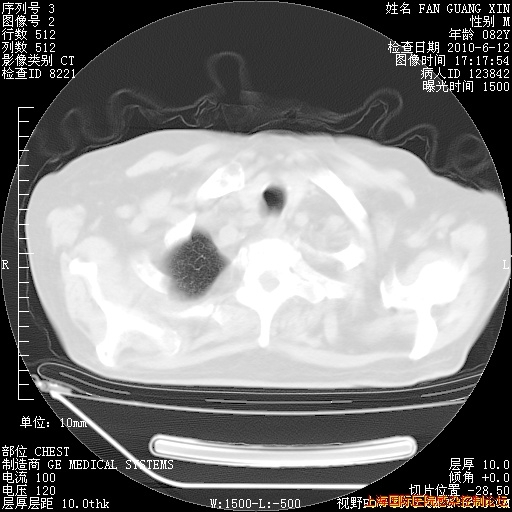

6月12日纵膈窗

6月10日改甲强龙80mg qd ,在南京年会期间体温不稳,18日有一次寒战后体温达39度。19日开始用甲强龙60mg bid ,加量后第二天就不发热。本打算在两周后即7月3日减量,但是7月2日洗澡受凉、发热、咳嗽、鼻音,口服复方大青叶片,甲强龙120mg用到9日(整整20天)。

自昨天起甲强龙改为80mg qd。

在抗结核治疗2周后一般情况逐渐好转。